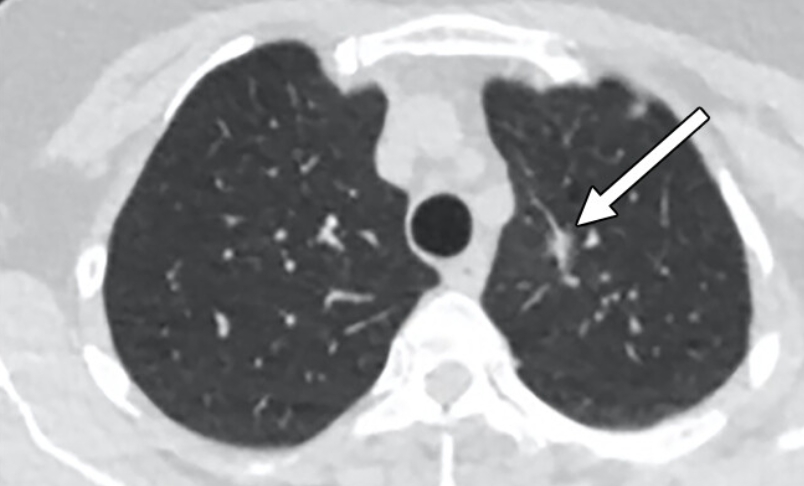

폐렴은 엑스레이에서 가장 자주 발견되는 질환 중 하나예요. 정상적인 폐는 까맣게 보이지만, 염증이 생기면 하얗게 변합니다. 의사들은 이를 보고 ‘침윤(염증이 번진 상태)’이라고 표현해요.

흉부 엑스레이로 알수있는것 폐렴의 종류에 따라 모양도 달라요. 한쪽 폐 전체가 하얗게 보이면 ‘엽성 폐렴’, 군데군데 얼룩처럼 보이면 ‘기관지 폐렴’일 수 있어요. 예전에 제 친구가 독감 후 기침이 너무 오래가서 병원에 갔는데, 엑스레이에 하얀 구름처럼 음영이 보여 폐렴 진단을 받았죠. 약을 꾸준히 먹고 다시 찍었을 땐 그 구름이 걷힌 것처럼 깨끗했어요. 이렇게 눈에 보이는 회복의 흔적이 참 다행스럽습니다.